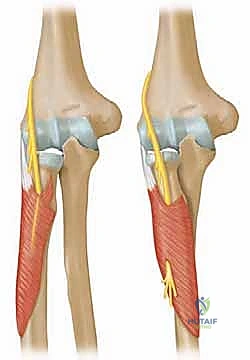

1. الرد المغلق والتثبيت عبر الجلد (CRPP - Closed Reduction and Percutaneous Pinning)

هذه هي التقنية السائدة والمفضلة عالمياً لعلاج كسور عنق الكعبرة لدى الأطفال (تقنية ميتازو Métaizeau Technique). وهي تقنية طفيفة التوغل لا تتطلب شقاً جراحياً كبيراً، مما يحافظ على الأنسجة المحيطة ويقلل من خطر الندبات وتيبس المفصل.